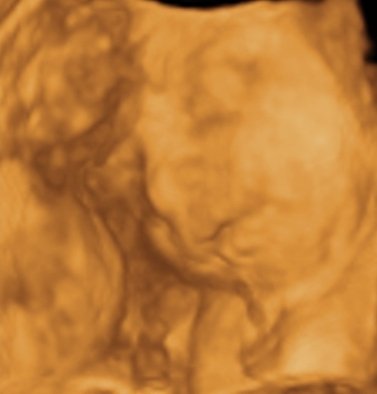

A mi kis álmodozónk